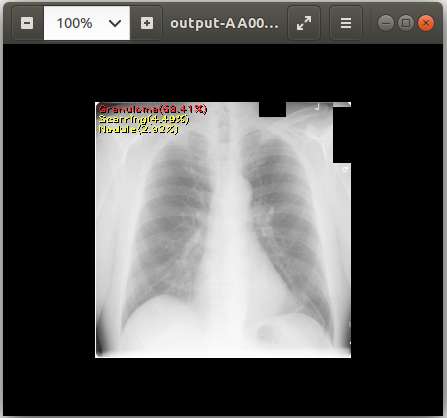

Output payload files are located under /operators/<operator name defined in the pipeline definition>/ folder. Since we triggered Chest X-ray Pipeline whose AI operator’s name is ai-app-chestxray, we can use the following command to download output files:

cat output-AA0007572607123433_v2.csv # View text output eog output-AA0007572607123433_v2.png # View image output using `eog` which is an image viewer available in Ubuntu

chest_xray_example_output.png